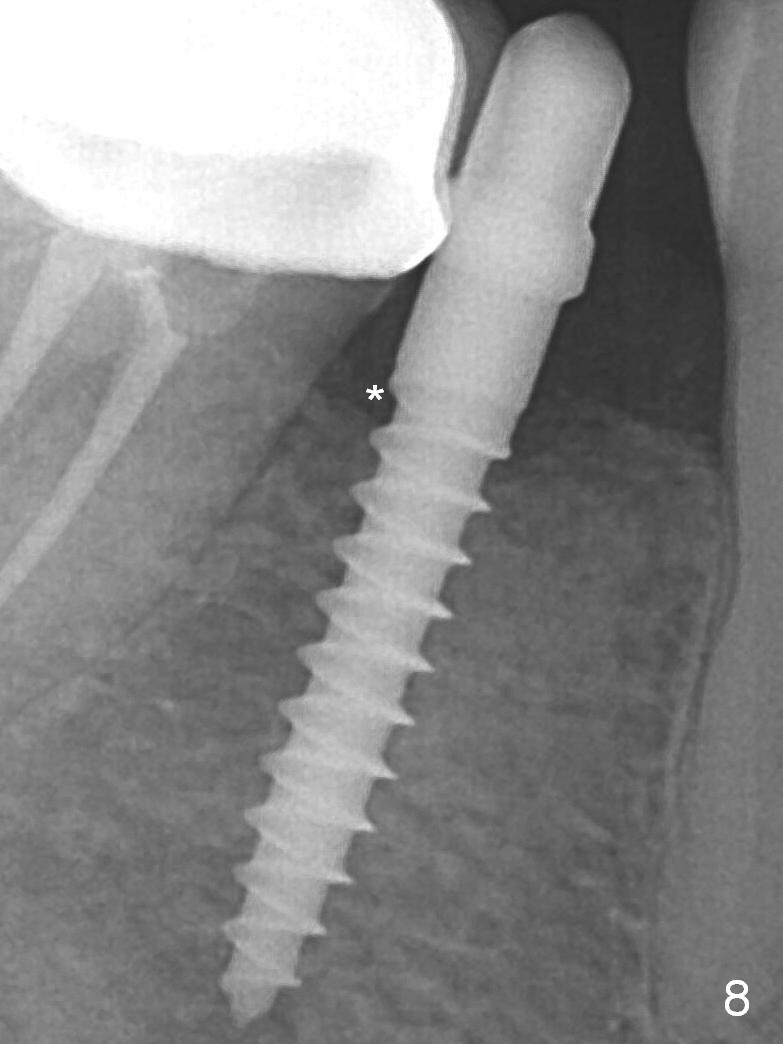

A 2.5x12(2) mm 1-piece implant is placed (Fig.6). There is mild bone loss distal 4 months postop (Fig.8 * (possible artifact due to angulation)).